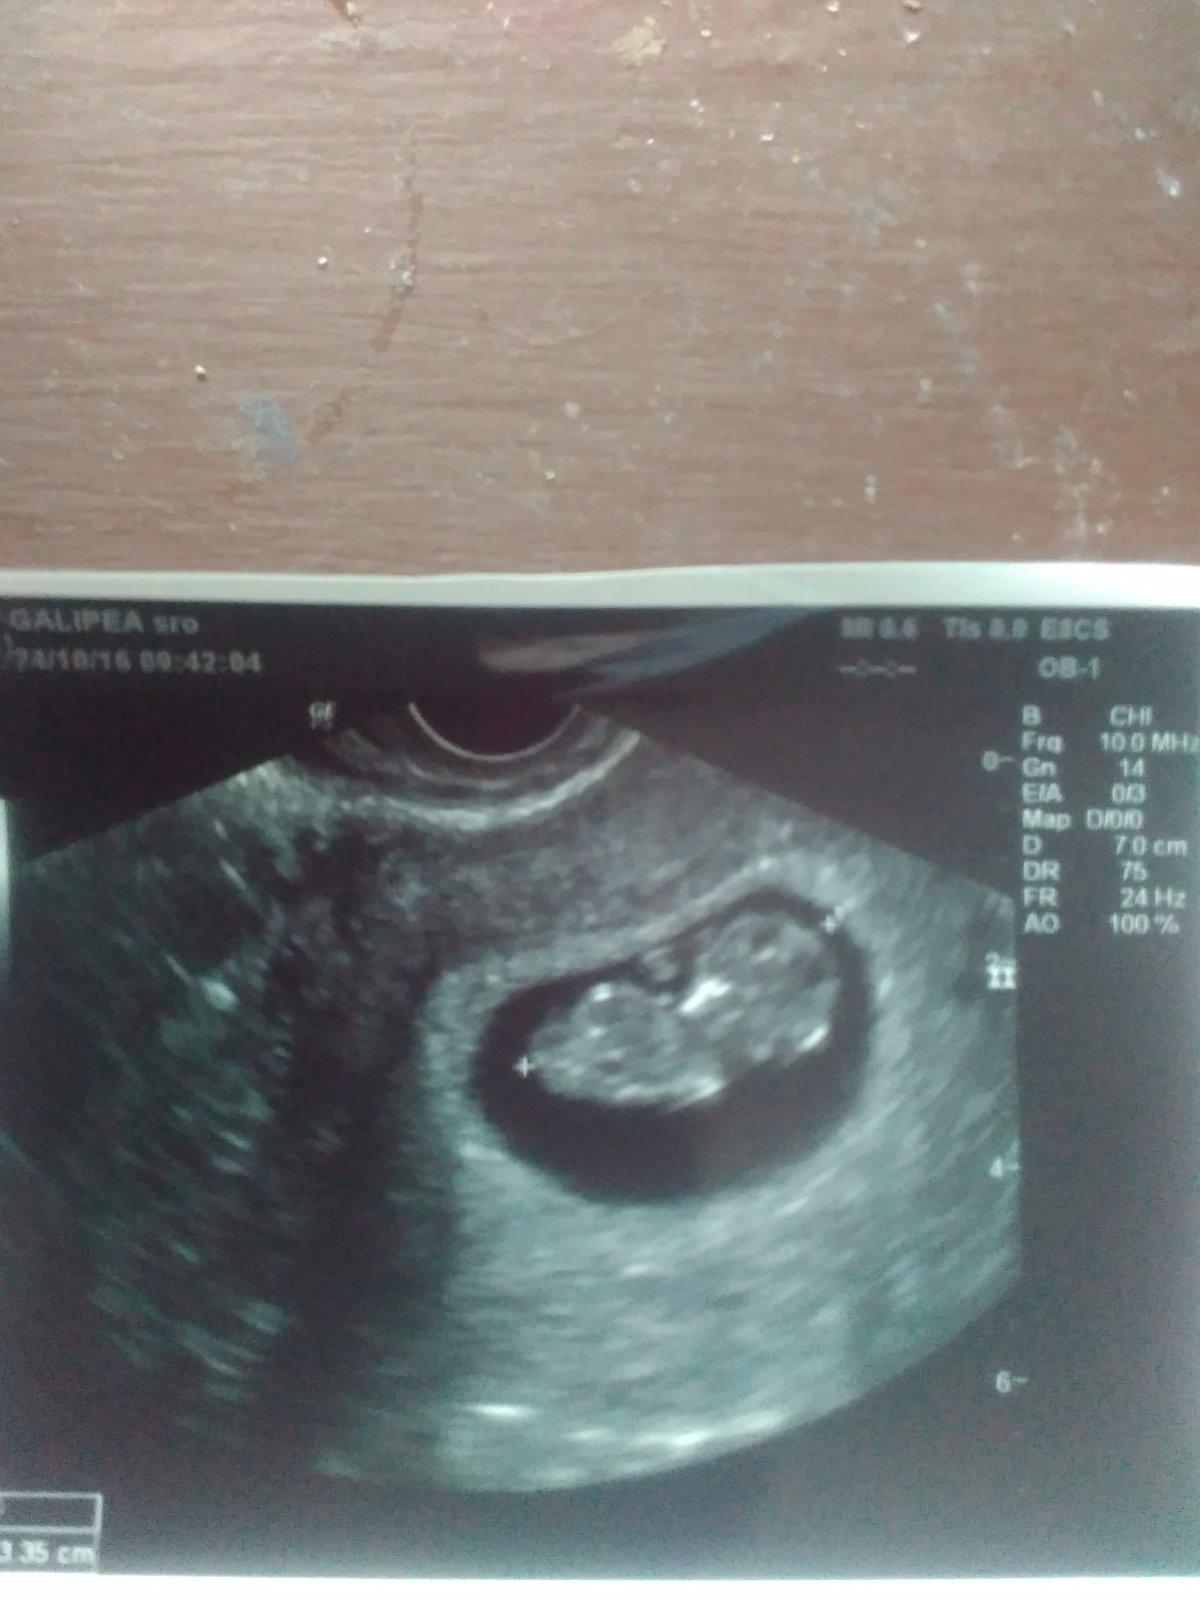

@mausy21 krása.... Ja pôjdem v pondelok....to budem 10+2tt som zvedavá ako bude vyzerať mimi

@cukruska1920 tak ja mám nakázané doniesť moč a prísť nalačno... tak to som tiež zvedavá za tie uplynulé týždne... predtým malo 1,5cm 🙂

@enusamt moje malo naposledy 1.9cm

Ahojteee...tak ja dnes konecne uz odisla z ambulancie s knižkou a fotkou...mame 4.4cm a sme 10+6tt...dalsia kontrola o 2 tyzdne..skrining..mooocc sa tesimee babo krasne kopkalo a mrvilo sa...